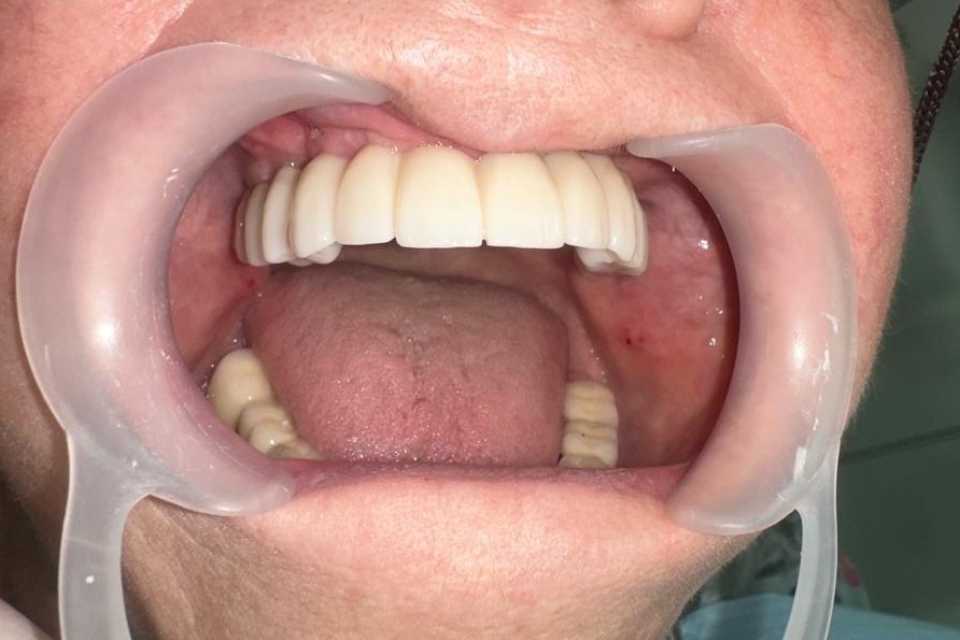

Sub anestezie generală s-au inserat 4 implanturi zigomatice și 2 implanturi pterigoide și 1 implant dentar normal cu ajutorul cărora am realizat o lucrare dentară protetică fixă din ceramica pe zirconiu insurubabila de 14 elemente.